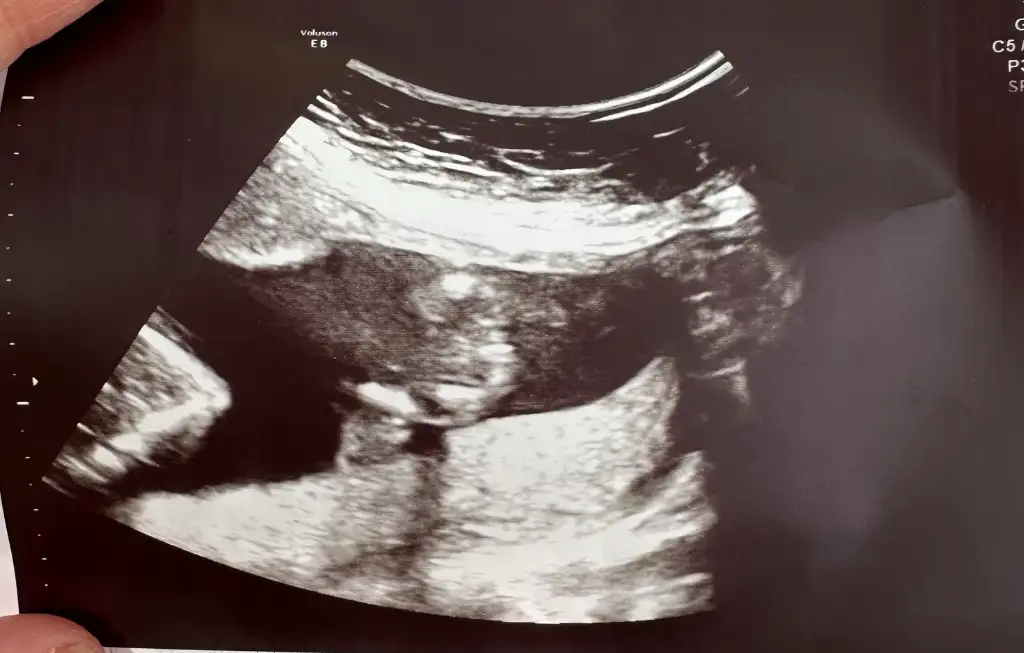

Bu resime göre 14 hafta bi kız dediler bi erkek sizce bu resimde cinsiyet nub teorisi olarak nedir?Normalde belli olması lazım